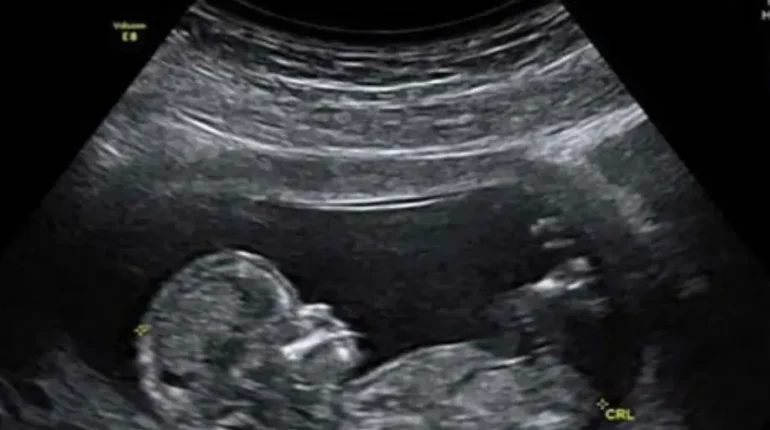

A groundbreaking study published in The Journal of Immunology reveals a surprising link between maternal gut microbiome and autism development in offspring. Researchers at the University of Virginia discovered that a specific immune molecule, IL-17a, may trigger autism-like symptoms when activated by certain maternal gut bacteria. Could understanding this biological pathway open new prevention strategies for neurodevelopmental disorders?